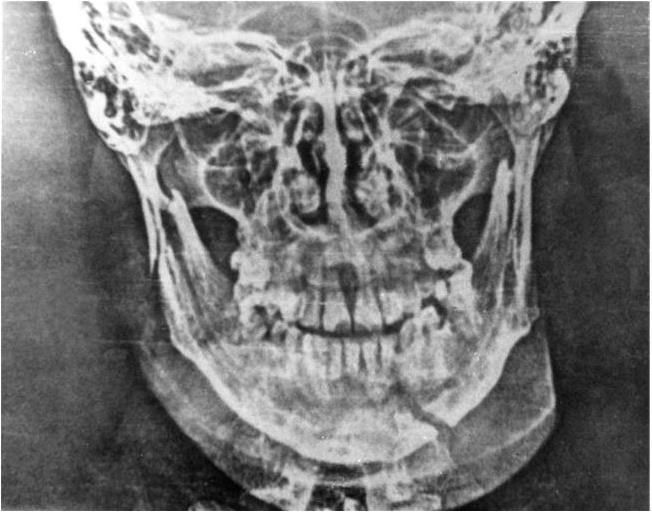

Рис. 6. Электрорентгенограмма нижней челюсти при переломе в области основания мыщелкового отростка справа и |34 зубов

В настоящее время широкое распространение получил метод рентгенографии без использования рентгеновской пленки – электрорентгенография. Получаемые при этом изображения нижней челюсти вполне удовлетворяют требованиям диагностики (рис. 6), а простота и возможность быстро получить отпечаток делают этот метод очень перспективным, особенно для военно-полевой челюстно-лицевой хирургии.